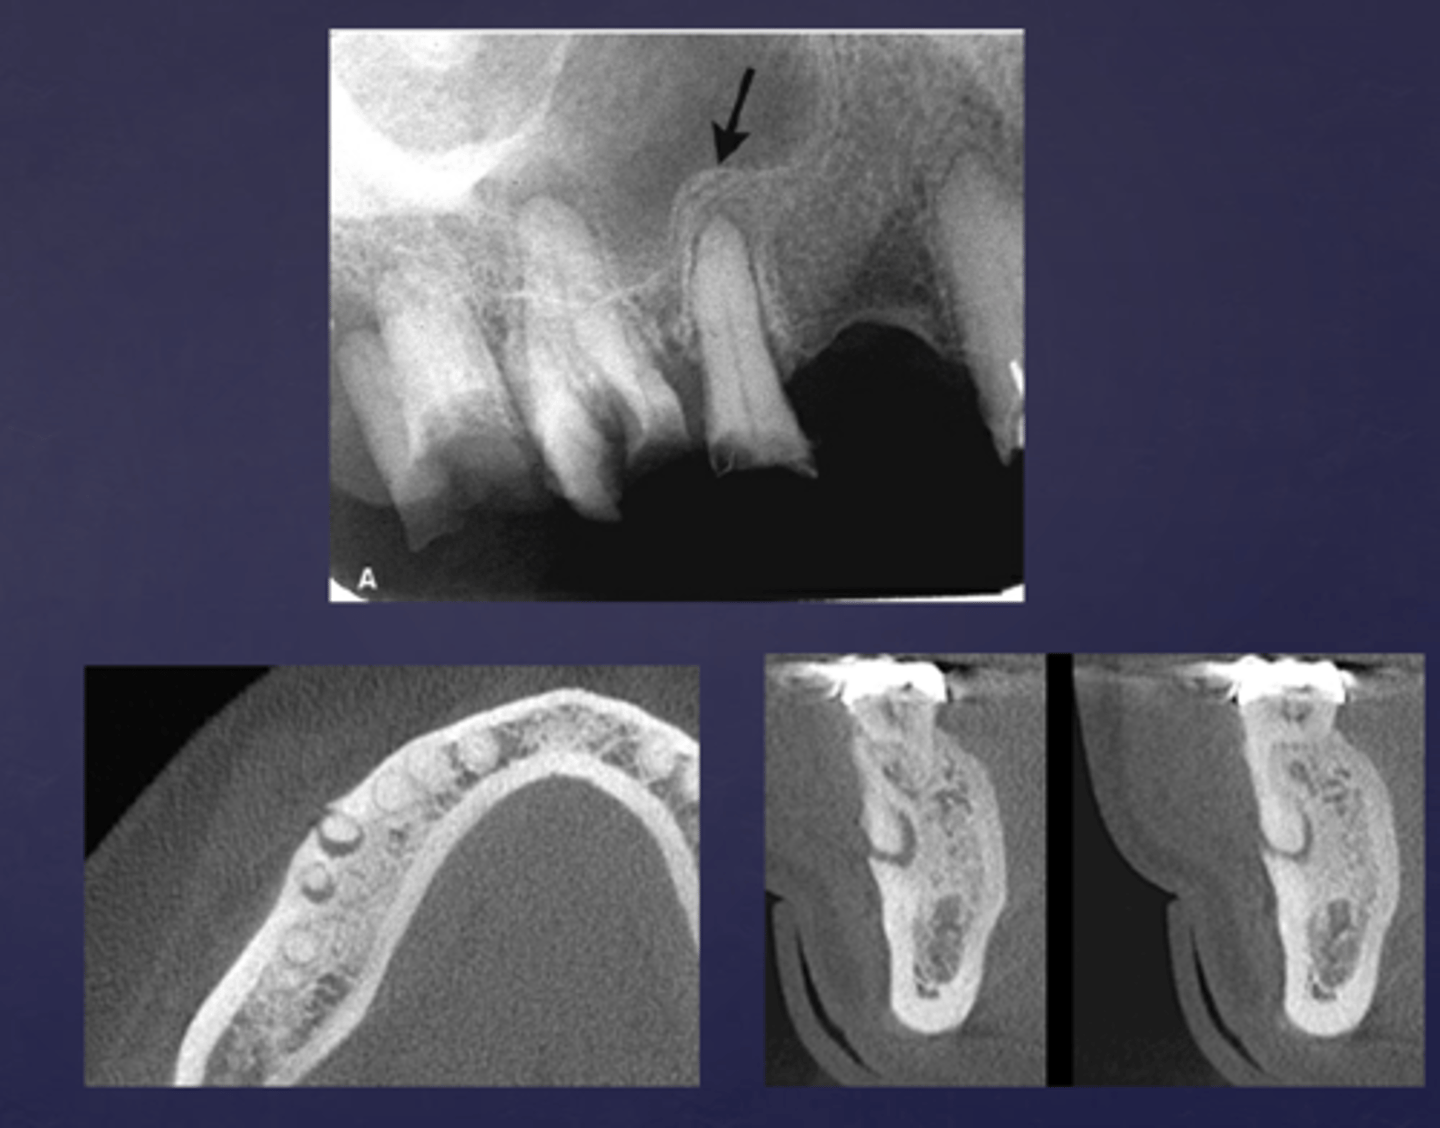

These arrows are pointing at what?

moth-eaten appearance of acute osteomyelitis

The moth eaten appearance is associated with what?

acute osteomyelitis, mixed radiolucent/radiopaque areas

What is the black arrow pointing at?

sequestrae

What is the white arrow pointing at?

periosteal reaction

periosteal reaction (increased bone density)

sequestra